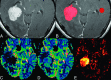

Background and purpose: Contrast leakage results in underestimation of the CBV of brain tumors. Our aim was to compare the diagnostic performance of DSC perfusion MR imaging without and with mathematic contrast-leakage correction in differentiating PCNSLs and glioblastomas.

Materials and methods: Perfusion parameters-CBV, corrected CBV, and leakage coefficient-were measured in enhancing tumor portions and contralateral NAWM of 15 PCNSLs and 20 glioblastomas, respectively. The ratios of CBV and corrected CBV were calculated by dividing the tumor values by those obtained from contralateral NAWM. A paired t test was used to compare tumor K2 and NAWM K2, as well as tumor CBV ratios without and with leakage correction. Comparisons of CBV, corrected CBV, and K2 between PCNSLs and glioblastomas were done by using a 2-sample t test. The diagnostic performance of DSC perfusion MR imaging without and with contrast-leakage correction was assessed with receiver operating characteristic curve analysis.

Results: PCNSLs and glioblastomas demonstrated higher K2 than those in their contralateral NAWM. Corrected CBV ratios were significantly higher than the uncorrected ones for both tumors. PCNSLs had lower CBV ratios (P < .001), lower corrected CBV ratios (P < .001), and higher K2 (P = .001) compared with glioblastomas. In differentiating between PCNSLs and glioblastomas, the area under the curve of the CBV ratio, corrected CBV ratio, and K2 were 0.984, 0.940, and 0.788, respectively.

Conclusions: PCNSL can be differentiated from glioblastoma with CBV ratios, corrected CBV ratios, and K2. CBV without contrast-leakage correction seems to have the best diagnostic performance in differentiating the 2 tumors.